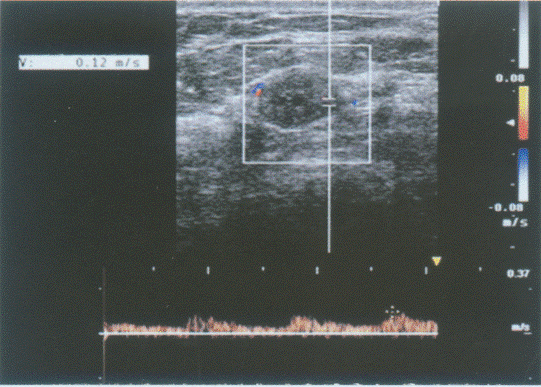

颈部扫查:请指出图1中测量为0.31cm的管径,彩图85(1)所指,彩图85(2)PW取样容积取样处分别是颈部哪条血管()。

A.椎动脉

B.甲状颈干动脉

C.颈总动脉

D.锁骨下动脉

44、单项选择题 经颅超声检测的声窗是()。①颞窗②枕窗③眼窗④额窗⑤顶窗⑥颞-额窗、额-顶窗、顶-枕窗、颡-枕窗